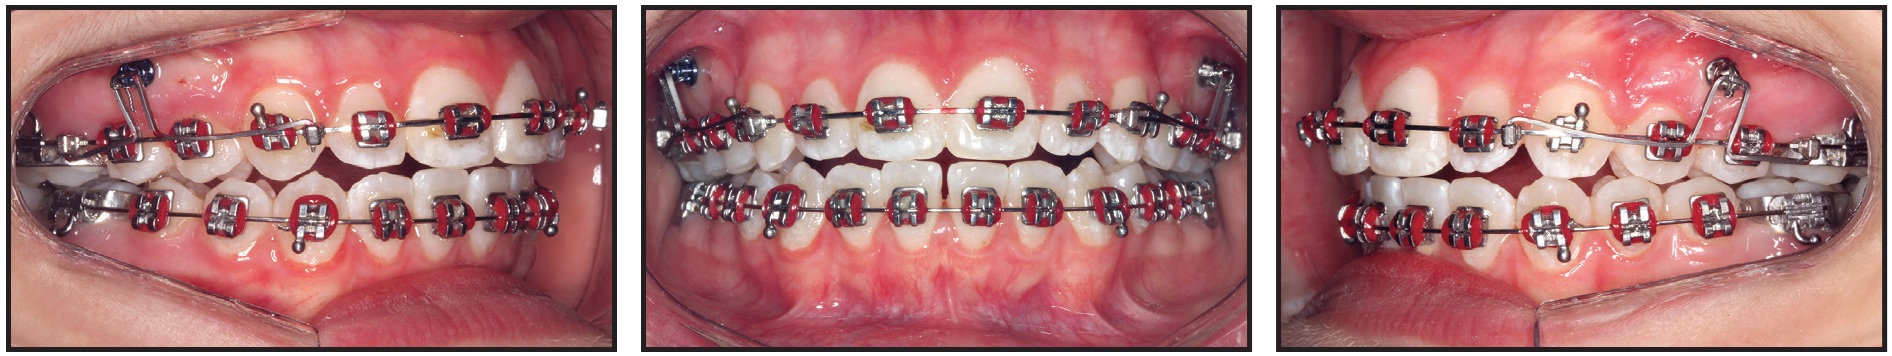

The DAVIT device was then kept passively in place for another two months to stabilize the dentoalveolar changes (Fig. 10).

Fig. 10 After two months of passive retention with DAVIT to stabilize changes.

Intermaxillary elastics were not prescribed to improve the overbite, posterior intercuspation, or anteroposterior relationship during the finishing phase. The fixed appliances and mini-implants were removed, and an upper Hawley and lower 3-3 fixed lingual retainer were placed for retention.

Total treatment time was 13 months (Fig. 11A).

Fig. 11 A. Patient after 13 months of treatment (continued in next image).

Excellent smile esthetics and a static and functional occlusion were obtained. The upper incisors were extruded and palatally tipped, while the upper molars were intruded. The occlusal plane underwent clockwise rotation, and the upper posterior teeth were uprighted. Consequently, the anterior open bite was closed, the overbite was overcorrected, and occlusal contact was established between the premolars. The Class I molar relationship and the posterior transverse relationship were maintained. The lower incisors were protruded to resolve the anterior crowding. External apical root resorption involved no more than slight rounding, which is considered clinically acceptable.39 The upper second molars were erupting toward the occlusal plane, but the left second molar showed a less favorable eruption axis; therefore, the patient was kept under observation to evaluate whether surgical intervention would be required (Fig. 11B).

Fig. 11 (cont.) A. Patient after 13 months of treatment. B. Superimposition of pretreatment (black) and post-treatment (red) cephalometric tracings.